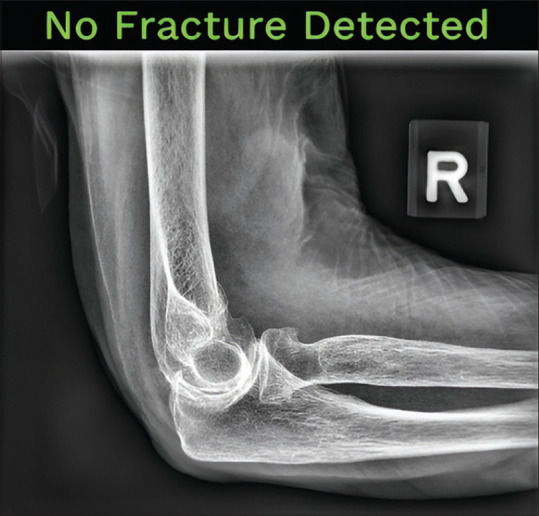

Introduction: Radiology plays an integral role in fracture detection in the emergency department (ED). After hours, when there are fewer reporting radiologists, most radiographs are interpreted by ED physicians. A minority of these interpretations may miss diagnoses, which later require the callback of patients for further management. Artificial intelligence (AI) has been viewed as a potential solution to augment the shortage of radiologists after hours. We explored the efficacy of an AI solution in the detection of appendicular and pelvic fractures for adult radiographs performed after hours at a general hospital ED in Singapore, and estimated the potential monetary and non-monetary benefits.

Methods: One hundred and fifty anonymised abnormal radiographs were retrospectively collected and fed through an AI fracture detection solution. The radiographs were re-read by two radiologist reviewers and their consensus was established as the reference standard. Cases were stratified based on the concordance between the AI solution and the reviewers' findings. Discordant cases were further analysed based on the nature of the discrepancy into overcall and undercall subgroups. Statistical analysis was performed to evaluate the accuracy, sensitivity and inter-rater reliability of the AI solution.

Results: Ninety-two examinations were included in the final study radiograph set. The AI solution had a sensitivity of 98.9%, an accuracy of 85.9% and an almost perfect agreement with the reference standard.

Conclusion: An AI fracture detection solution has similar sensitivity to human radiologists in the detection of fractures on ED appendicular and pelvic radiographs. Its implementation offers significant potential measurable cost, manpower and time savings.